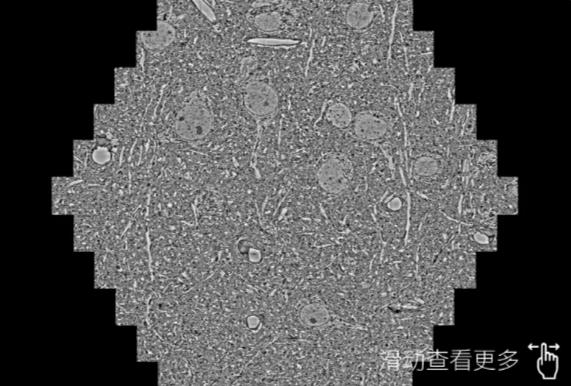

鼠脑切片。左图使用亳州蔡司亳州扫描电镜MultiSEM706对165μmx143pm面积区域成像,耗时仅需1.5秒。右图为鼠脑切片中30μm区域放大效果。样品由芝加哥大学B.Kasthuri提供。

使用蔡司高速亳州扫描电镜MultiSEM对1mm²人脑皮层组织进行高分辨成像,并对其中的各种细胞结构进行三维重构分析。左图展示了2x3mm²组织平面中锥体神经元的三维重构效果。右图显示了局部体积神经元三维重构。图像由哈佛大学chtman实验室提供,渲染图由D. Berger 制作。